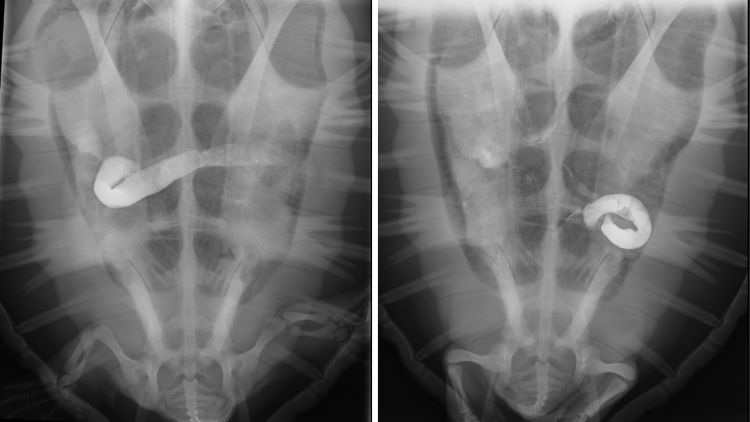

Alvi the green turtle's life was saved when a barium contrast study revealed a plastic bag stuck in his oesophagus.

Because turtles have very slow metabolisms, they can go weeks or even months without pooping. This makes it difficult to know if a new arrival at the rescue clinic is facing something serious, like gut stasis caused by injuries from ingested plastic, or is just a little stressed, but otherwise fine. Because of their hard shells, there is no easy way to see inside a turtle...

Barium studies allow the veterinary team to examine an animal's gut - something that would not normally be visible in X-ray images. Here we can see the isotope moving through Harry.

That's where X-rays come in. The Two Oceans Aquarium's veterinary clinic is at the disposal of the turtle team, who can use it to carry out a "contrast study" - a procedure where a turtle is fed a material (barium in our case) that reflects X-rays. This allows the team to see the fluid as it moves through a turtle's gut, and help find any internal injuries - allowing the team to make informed care decisions!